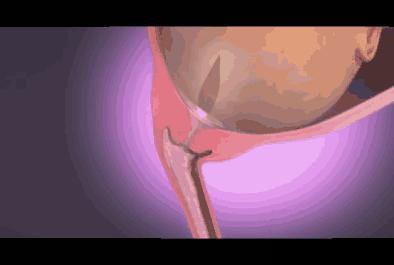

是指怀孕时子宫羊膜腔内的液体。在整个怀孕过程中,它是维持胎儿生命所不可缺少的重要成分。在胎儿的不同发育阶段,羊水的来源也各不相同。在妊娠第一个三月期,羊水主要来自胚胎的血浆成分;之后,随着胚胎的器官开始成熟发育,其他诸如胎儿的尿液、呼吸系统、胃肠道、脐带、胎盘表面等等,也都成为了羊水的来源。